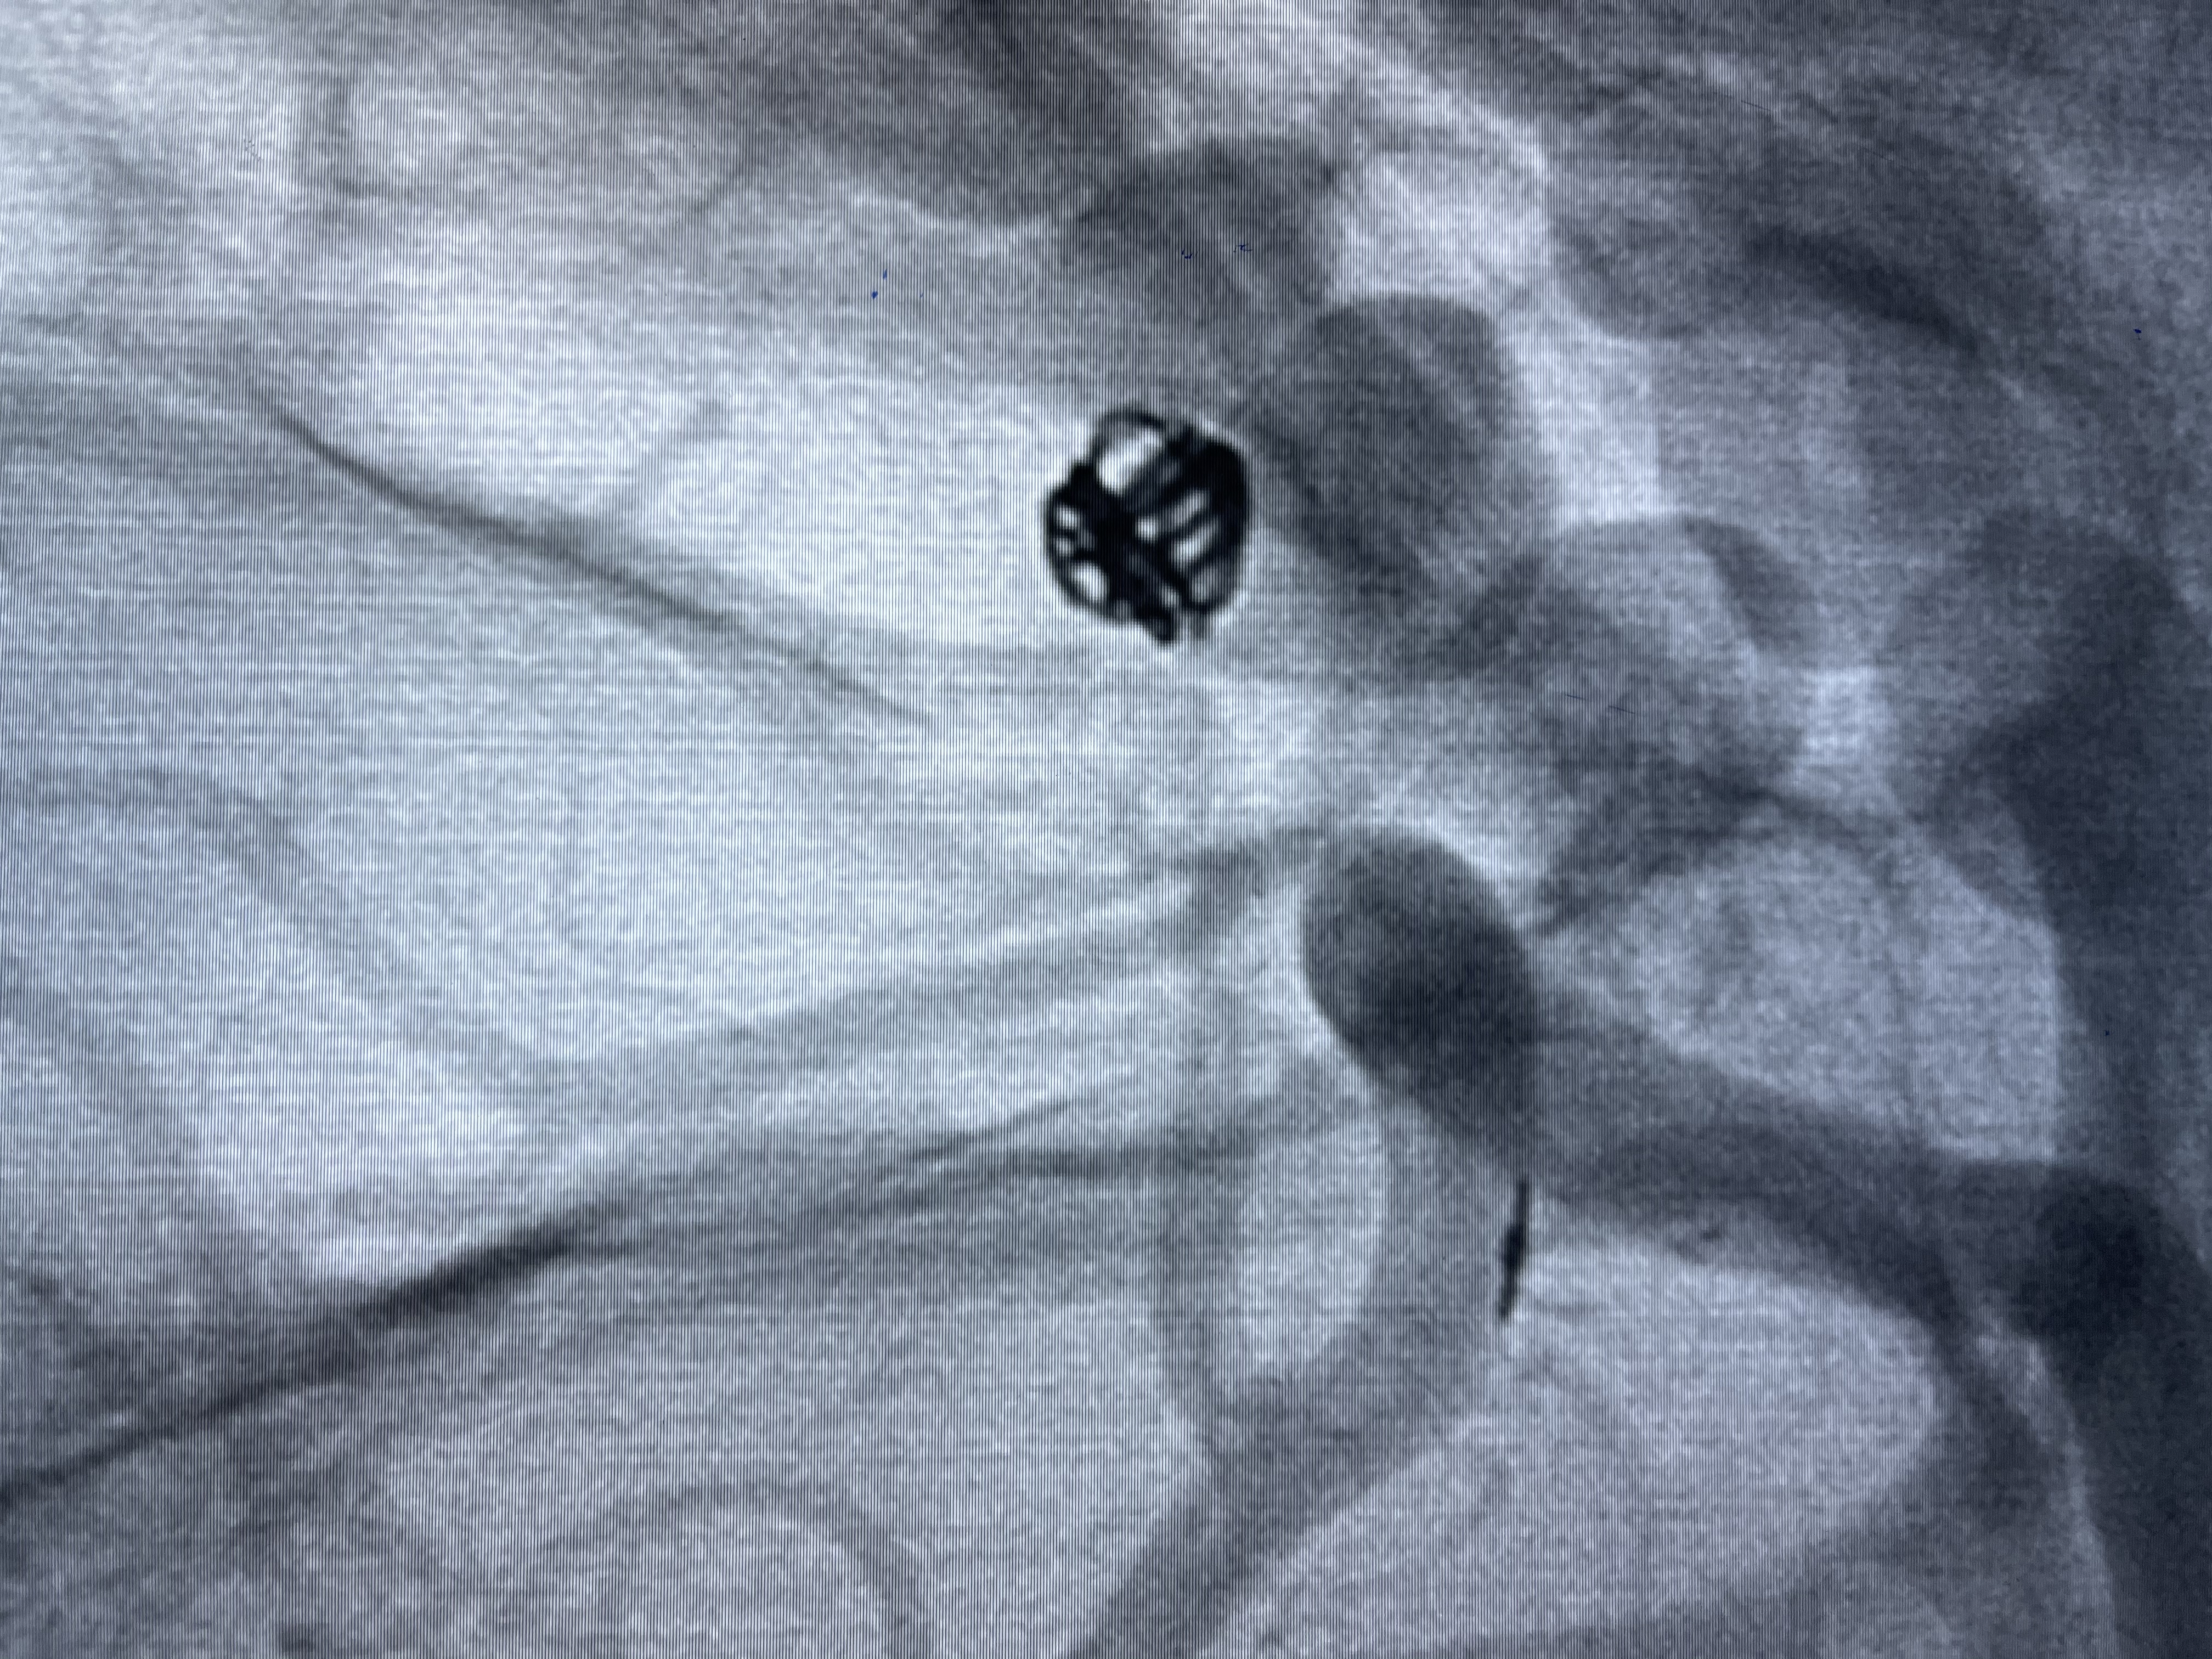

2021-01-11全麻下双微导管栓塞

5-15cm三维圈成篮:瘤颈部覆盖弹簧圈